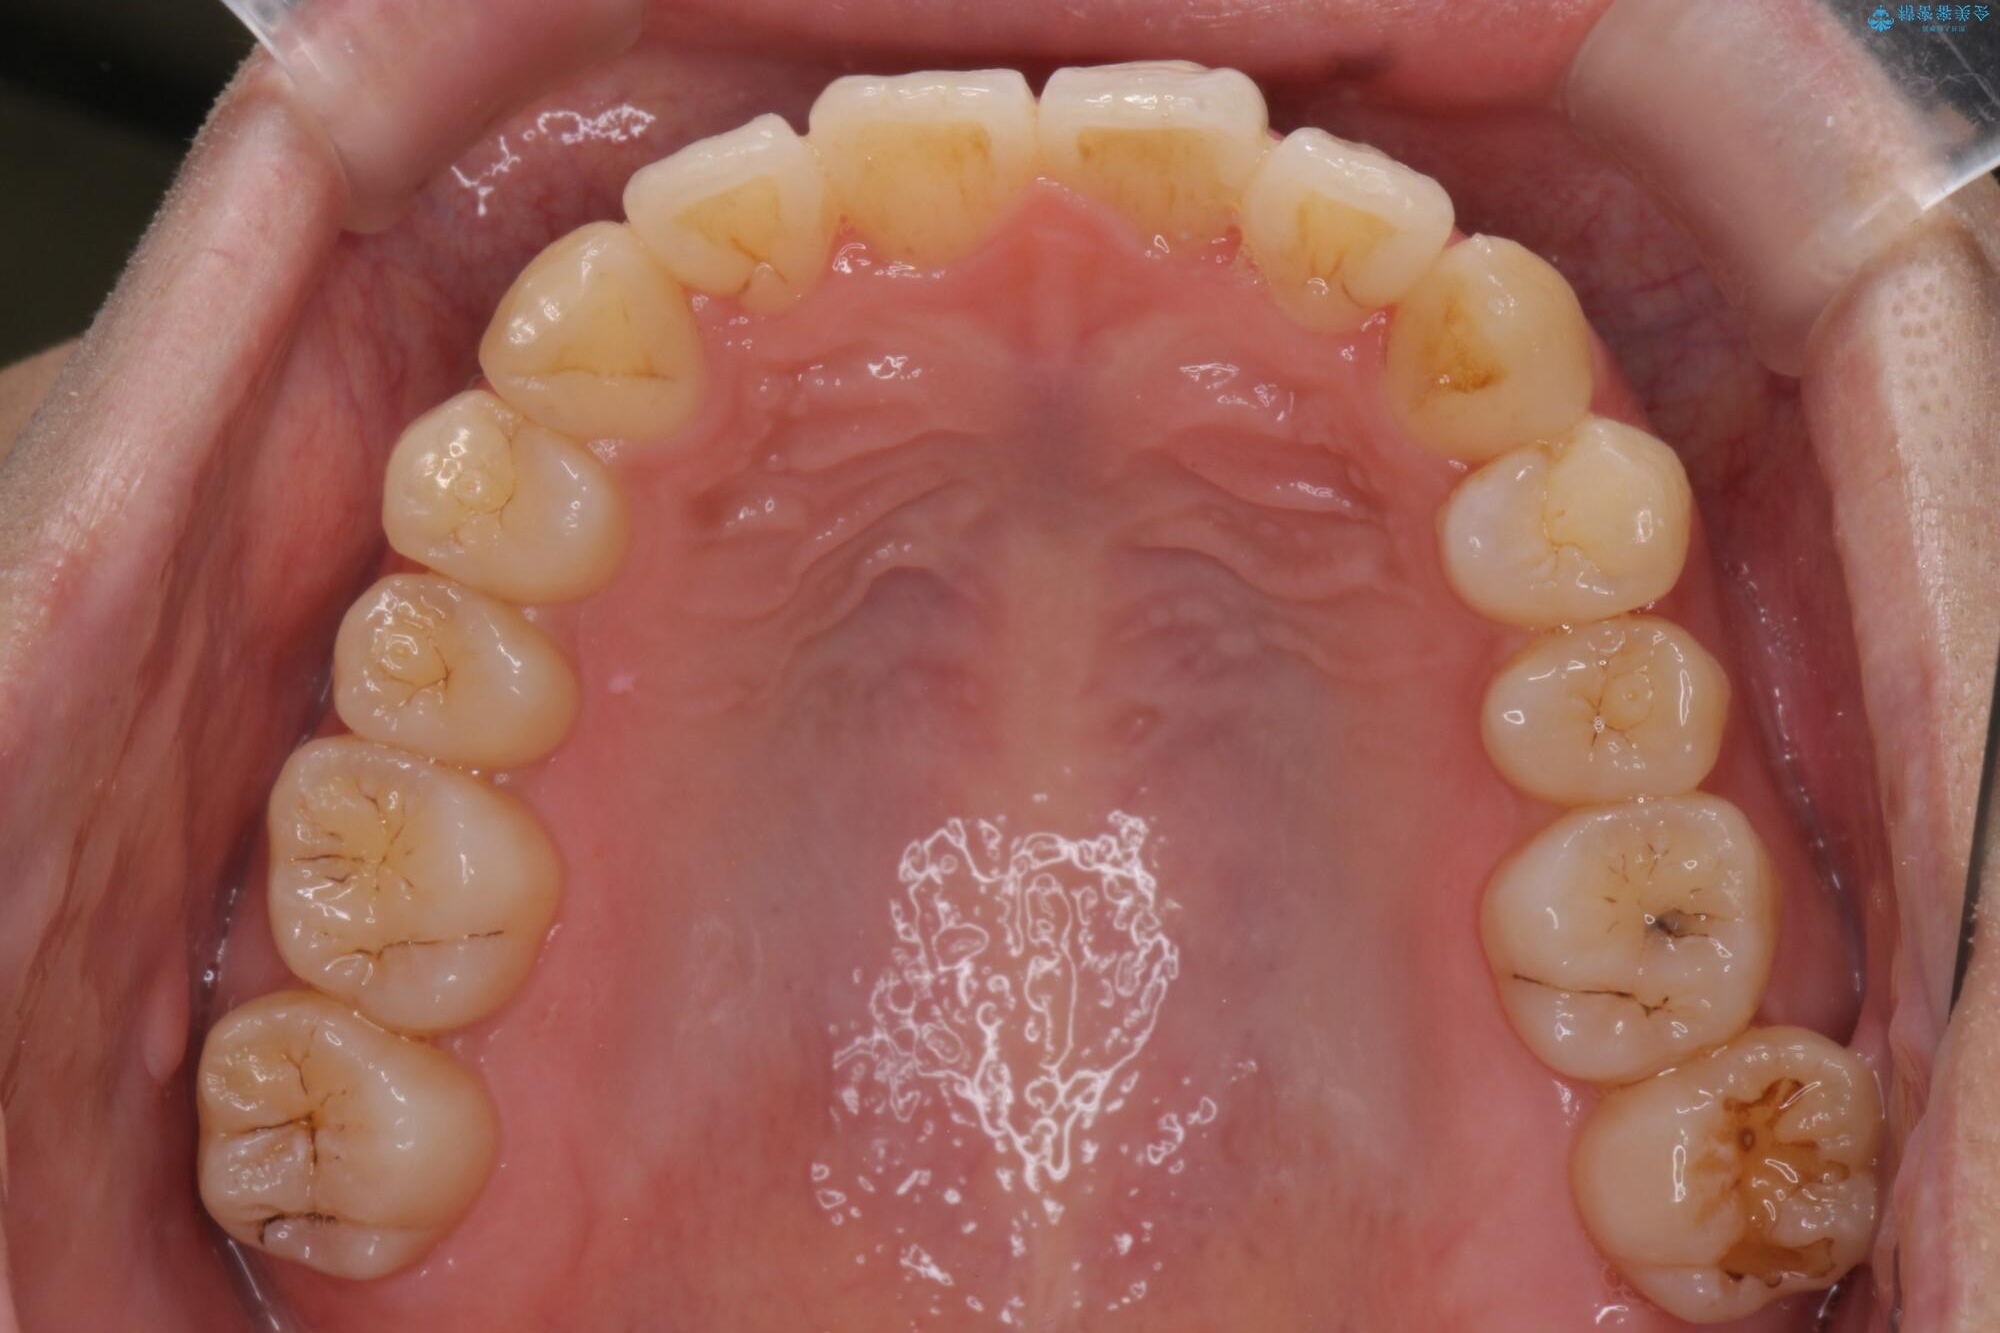

前歯のガタつきの改善を主訴にご来院されました。 特に犬歯の傾きが気になるとのことでした。

犬歯がかなり手前に傾いていましたが、ガタつきはそれほど強くないため非抜歯でマウスピース矯正が可能と判断しました。

治療前

気になる犬歯のガタつきをマウスピース矯正で改善 治療前画像 気になる犬歯のガタつきをマウスピース矯正で改善 治療前画像 気になる犬歯のガタつきをマウスピース矯正で改善 治療前画像 気になる犬歯のガタつきをマウスピース矯正で改善 治療前画像